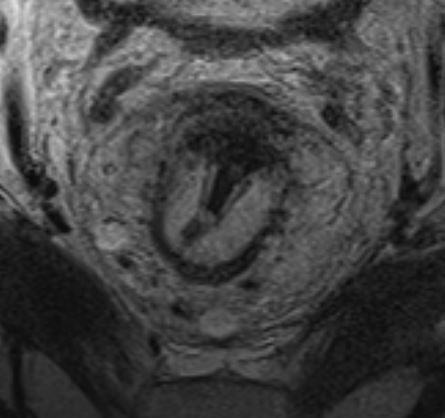

Протяженность опухоли и ее распространение по окружности описывается в условных «часах циферблата». На МРТ опухоль прямой кишки проявляется локальным утолщением стенки кишки с закругленными приподнятыми краями (рис. 2).

Высокоразрешающие Т2-ВИ срезы в корональной плоскости (по длинной оси анального канала) детально визуализируют распространенность опухолевого процесса и обеспечивают информацией, необходимой для выбора хирургического подхода.

Классификация для стадирования низкорасположенных опухолей (табл. 2) должна дополнительно применяться при описании распространенности опухолевого процесса. Данная классификация критически важна для определения показаний к межсфинктерной резекции или БПЭ, поскольку учитывает вовлечение:

сфинктера (внутреннего, наружного)

межсфинктерного пространства

- levator ani

расстояние до кожи промежности и m. puborectalis.